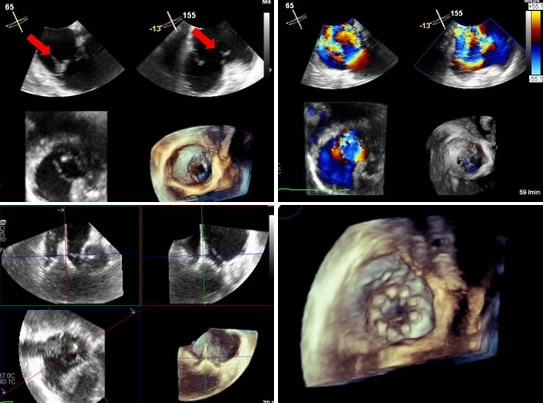

The superior-posterior transseptal puncture was performed under echocardiographic and fluoroscopic guidance. The first MitraClip was carefully advanced into the left atrium. It could not be directed toward the valve plane. Echocardiography showed a position in the atrial roof with minimal pericardial effusion. With gentle pulling maneuvers, we could clearly see that the clip could not be mobilized. We anticipated that severe pericardial effusion might occur and prepared a CellSaver and two erythrocyte concentrates as a preventive measure. Then we decided to place the clip in that position ready for pericardial puncture. After releasing the clip, pericardial effusion developed slowly, indicating a rather small defect in the left atrial roof. Pericardial puncture was performed, followed by manual autologous retransfusion and transfusion of the erythrocyte concentrates. Once continuous autotransfusion using CellSaver had been established, the procedure was continued. The severe mitral valve insufficiency was reduced to trace by implanting two MitraClips. Autotransfusion using CellSaver could be terminated after two hours, and the pericardial drainage could be removed after two days. Subsequently, weaning from the ventilator was accelerated and there were no further episodes of pleural effusion or pulmonary edema. After 50 days in our intensive care unit, the patient was transferred to neurological rehabilitation. He is currently undergoing walking training there.